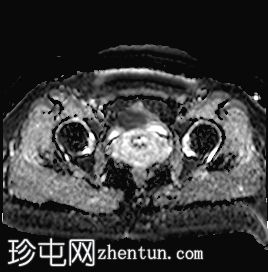

轴位

DWI序列

可见子宫外腹腔内妊娠囊,内含胎儿组织。

该妊娠囊向后推移子宫,并与剖宫产瘢痕凹陷处紧密相连。

该妊娠囊与相关肠袢无法分离。可见其与性腺血管密不可分,且性腺血管明显突出。

胎盘位于妊娠囊后方,紧贴子宫前壁。

沿妊娠囊下缘可见一处异质性局灶性积液,最大轴向尺寸约为 8.4 × 5.5 cm,T1 加权像呈异质性高信号,T2 加权像呈异质性中等信号,T1 脂肪抑制序列未见信号下降,提示为血液成分。该积液压迫膀胱。

可见周围脂肪间隙呈条索状改变。

左侧卵巢无法辨认。

右侧卵巢未见实性或囊性肿块。

子宫体积增大,后倾,子宫内膜厚度约 1 cm,子宫下段前壁可见局灶性变薄(既往子宫瘢痕)。子宫连接区完整,未见肌层肿块。可见子宫内膜腔边缘有血性分泌物。